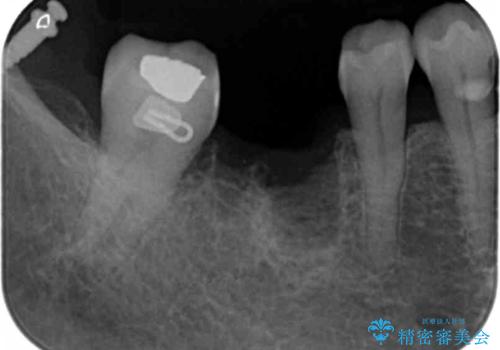

抜歯を行ったのち前後の歯に軽度の動揺があるため、インプラントではなくブリッジによる補綴処置を行い機能回復を行いますが、近心傾斜した第2大臼歯をマイクロインプラントを用いた小矯正を行うことで歯軸方向を改善し、神経を温存した状態でブリッジ製作できるよう前処置を行います。

ブリッジが長く機能できるように噛み合わせの微細な調整は非常に大切ですが、支台となる歯の神経を温存できるかどうかも非常に大きな要因です。

今回の治療ではブリッジ製作に先んじて小矯正を行うことで、より予知性を高める治療をおこなうことができました。